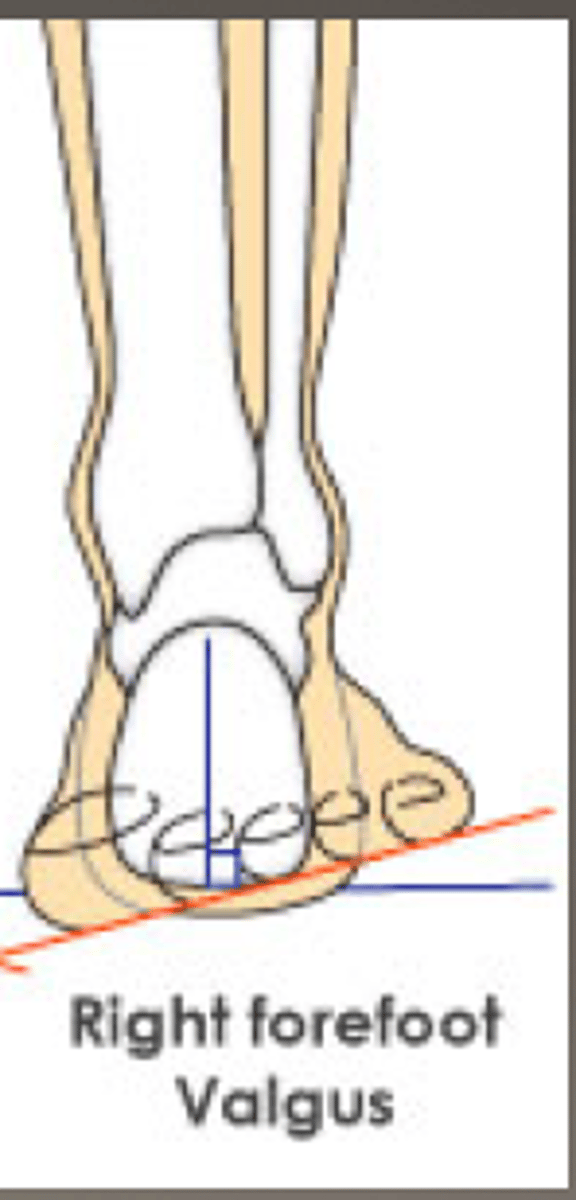

forefoot varus

- inversion of forefoot

- subtalar joint in neutral

forefoot valgus

- eversion of forefoot